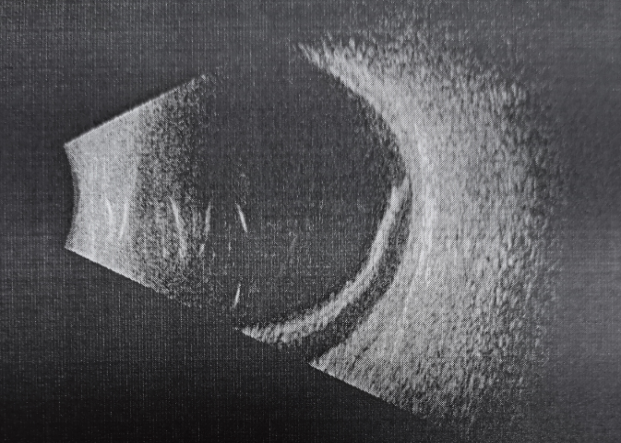

11岁的轩轩是个热爱运动的帅气小男生,一年前左眼被篮球砸伤,出现视物模糊,视力下降,因为担心被父母责骂,并未告知父母,直到体检发现左眼视力下降明显,影响到了自己的生活和学习,在父母的陪同下来到合肥普瑞眼科医院就诊,经检查诊断轩轩为左眼孔源性视网膜脱离。

视网膜,这个名字听起来有些生僻,但它却是我们视觉系统的核心部件。就像一台精密的相机,眼睛捕捉光线,视网膜则负责将这些光线转换成图像,传递给大脑,让我们看到这个世界。视网膜是一层非常薄的膜,但它还可以分为十层结构。其中,靠内侧的九层合起来,叫做神经上皮层,最外面一层叫色素上皮层。我们所说的视网膜脱离,并非是整个视网膜掉下来,而是视网膜内九层与外一层分离了。如果视网膜出现问题,就好比相机的底片受损,图像就会变得模糊不清,甚至完全消失。

高度近视患者的眼轴比普通眼睛长,眼球比正常人大。随着眼轴拉长,球壁会变薄,周围血管变细,血供差。周围的视网膜组织会出现变性区域和小孔,临床上称为视网膜裂孔。一旦出现裂孔,玻璃体会沿裂孔渗漏到视网膜下,顶起视网膜,使视网膜色素上皮层与神经上皮层分离,出现视网膜脱离,患者出现明显的视野缺损、视力下降等。

已经发生视网膜脱离的患者需要手术治疗。手术可以根据视网膜裂孔的位置、数目,大小,视网膜脱离的范围,时间,视网膜周围有无牵拉及玻璃体液化的程度分为内路和外路手术。内路手术主要是玻璃体切割术联合视网膜复位手术及激光光凝术,是从眼球内进行手术。外路手术主要是巩膜外压术和巩膜环扎术,从巩膜外进行手术,不进入眼球内部。